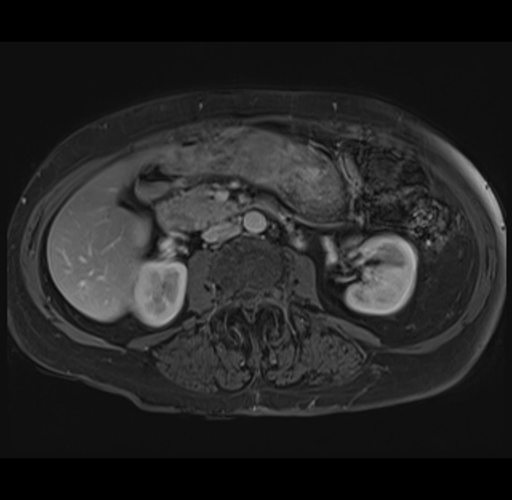

MRI T1

Imaging analysis